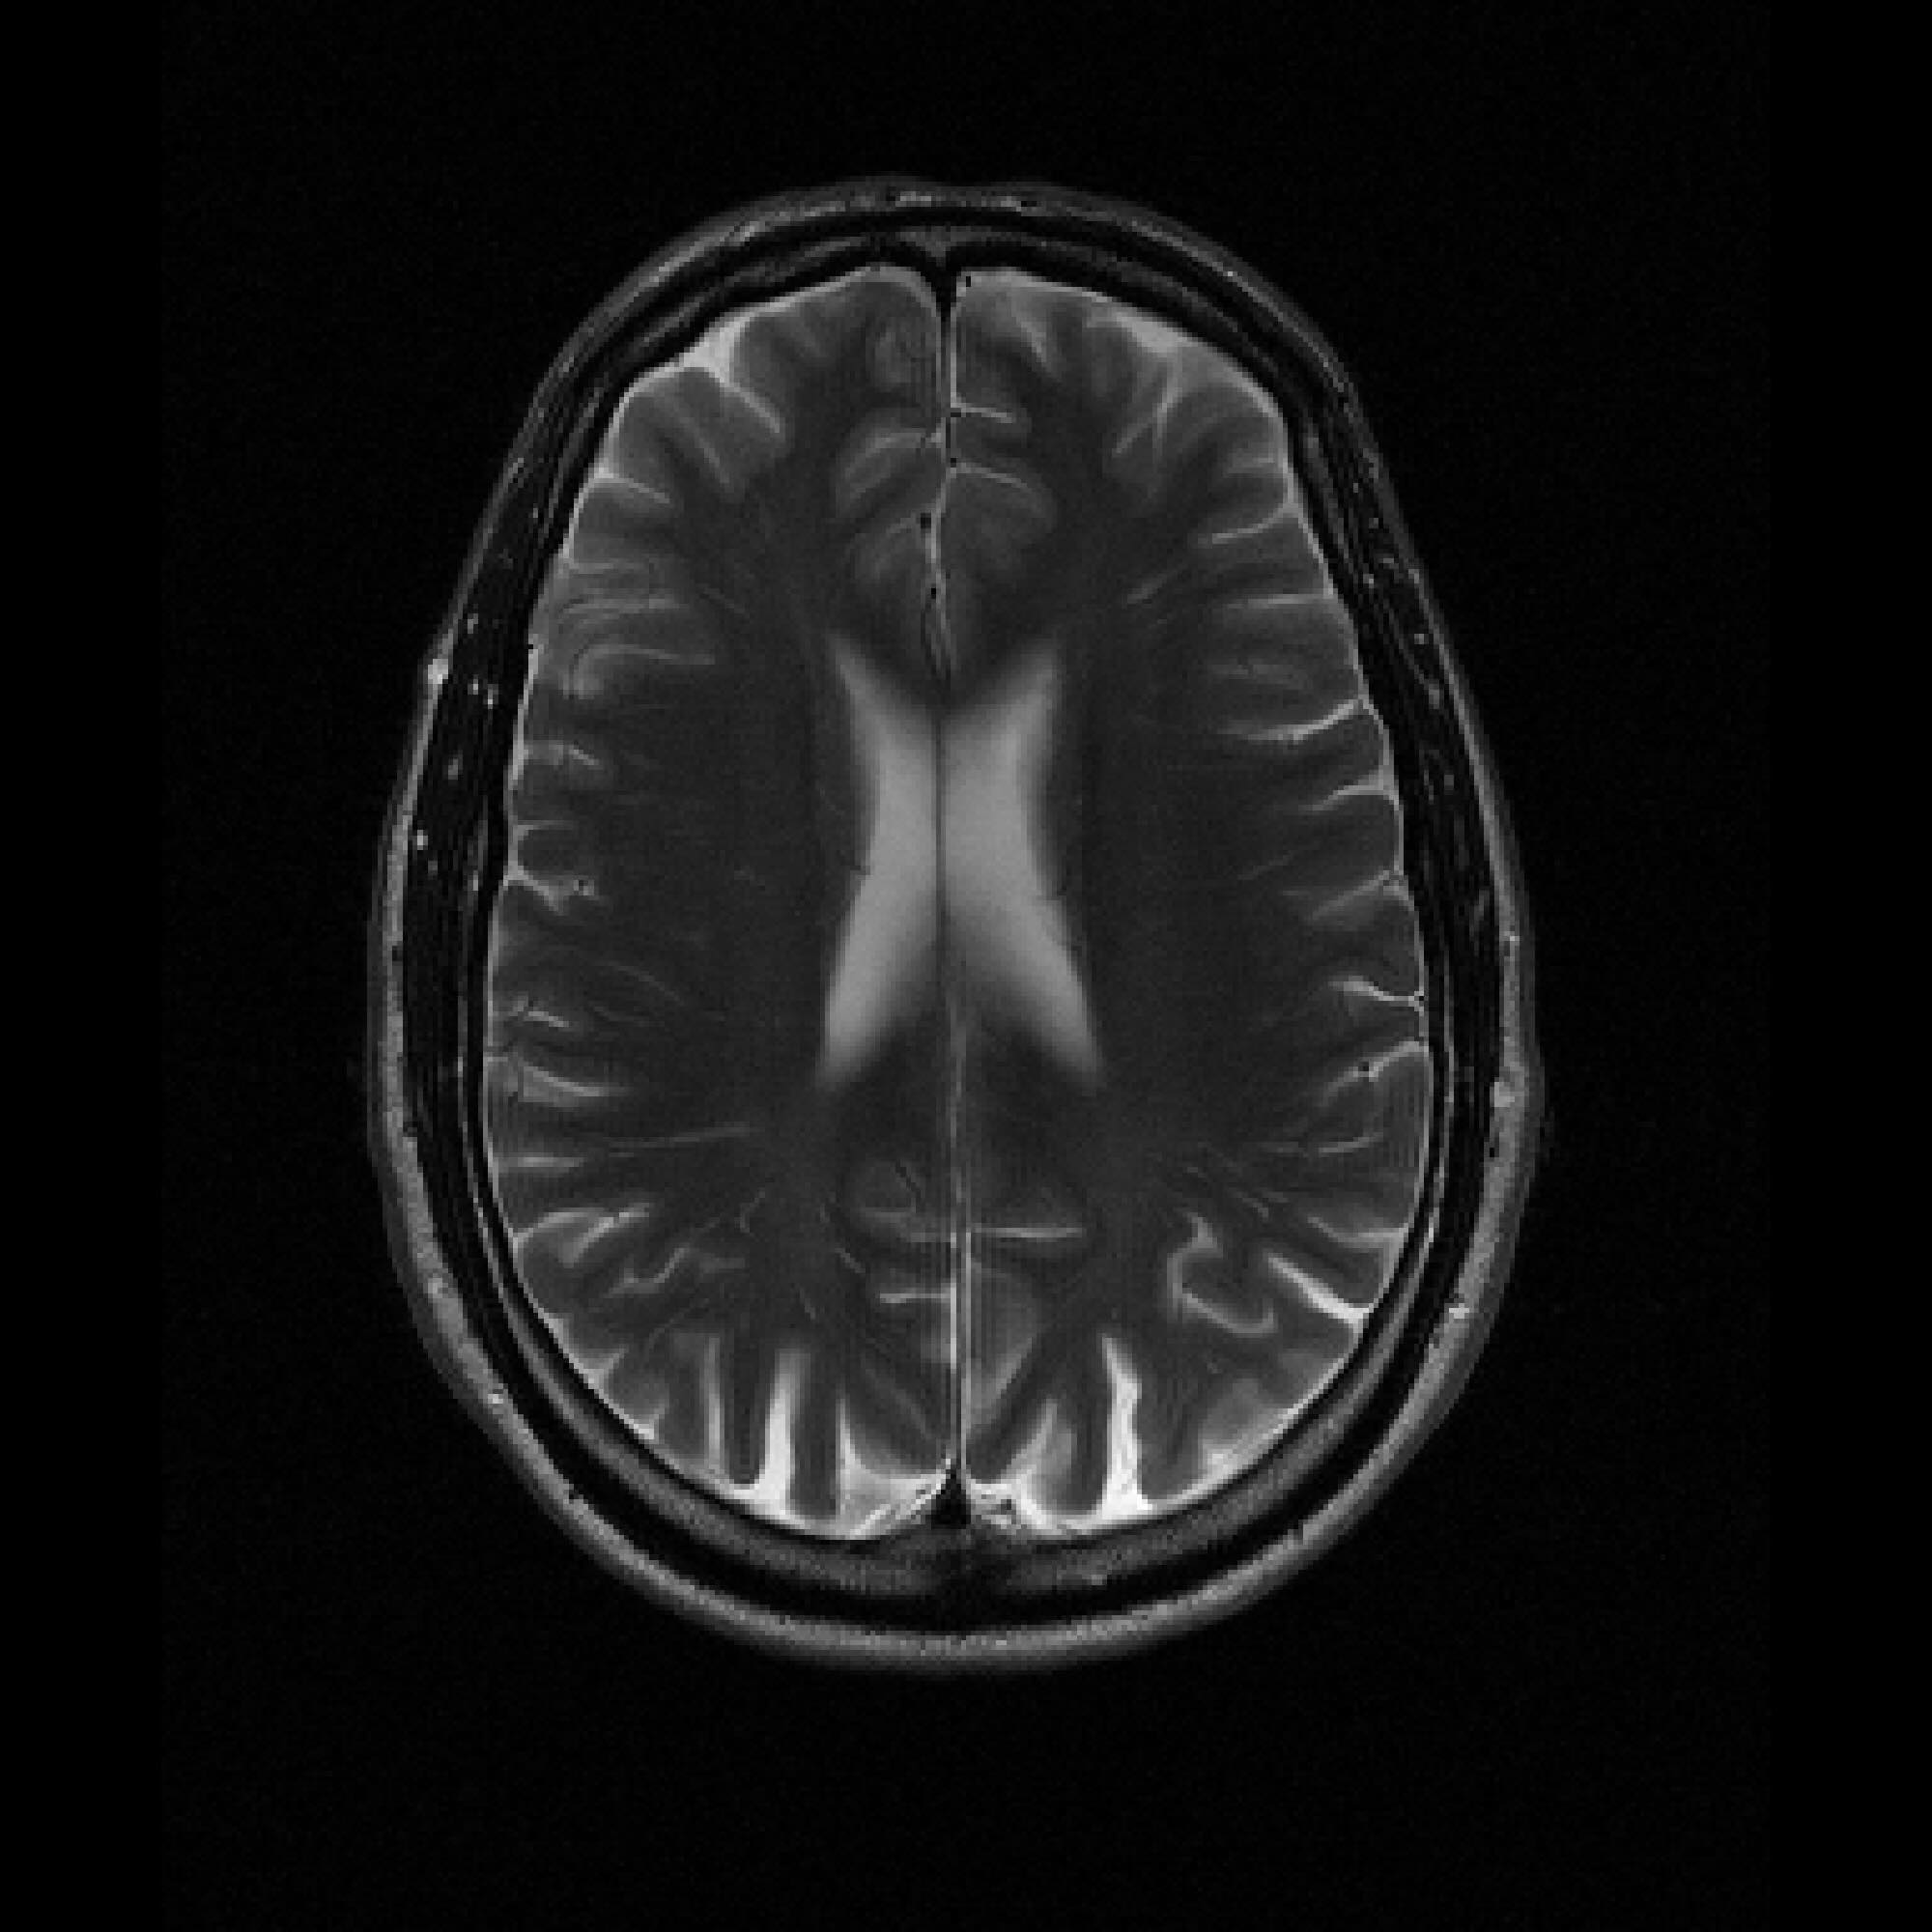

Figure 2: Example MRI magnitude reconstructions with S=25S=25 training slices at acceleration factor R=7R=7. PaDIS-MRI reconstructions are sharper and more faithful to the fully-sampled ground truth. Insets are shown to highlight detail.

Figure 2 provides a visual comparison of the reconstruction quality of each method on example slices. In reconstructions from the S=25,R=7S=25,R=7 models, FastMRI-EDM exhibits slightly more blurring and loss of fine structural details, particularly in regions with complex anatomical features. PaDIS-MRI, in contrast, preserves sharper boundaries and finer details. This enhanced data efficiency can be attributed to the patch-based prior’s ability to learn localized structural motifs more effectively from limited examples. Figure 6 in the Appendix shows similar reconstructions at S=200,R=7S=200,R=7 where FastMRI-EDM more closely approaches the performance of PaDIS-MRI but still struggles with highly detailed anatomy. At both dataset sizes, MoDL underperforms the diffusion priors. In Figure 2, MoDL’s FLAIR reconstruction exhibits pronounced artifacts, likely reflecting reduced generalizability of a supervised prior when the training distribution underrepresents FLAIR.